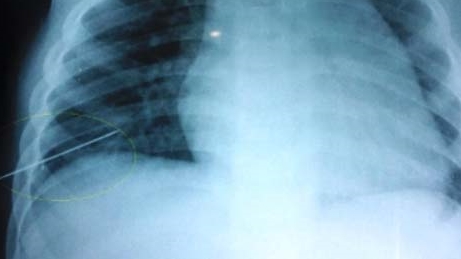

Ngày 3/5, các bác sỹ Bệnh viện Hữu nghị Việt Nam - Cuba Đồng Hới, Quảng Bình cho biết, sức khỏe của cháu Trần Chương Sỹ Cường (3 tuổi), trú xã Hoàn Trạch, huyện Bố Trạch, tỉnh Quảng Bình, đã bình phục tốt.

Mẹ cháu bé dùng kim may quần áo và đánh rơi kim xuống giường ngủ, và không may chiếc kim dài 5cm này đã đâm thấu ngực cháu trong lúc nằm ngủ.